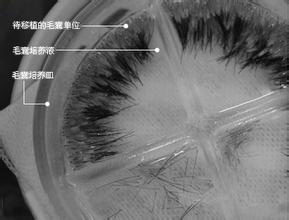

①专业检测,美学设计:运用美国HD毛囊检测仪,对脱发区及供体区进行精确的毛囊检测,直观的了解毛发问题所在;并根据检测数据,确定脱发级别、毛发种植的数量和供区提供的可移植的毛囊数量;再根据发友的脸型和气质,按“三庭五眼”黄金分割比例进行美学设计。

②三维一体,自然美观:在提取毛囊时,进行选择性提取,手术后提取区毛发与原状态无差异;单株分离后,在种植区选择性种植,并分层次多角度种植,利用1.0mm宝石刀+微针种植+PRP注射,达到脱发区域、供体部位、原有毛发三大区域三维一体,自然美观。

③专利设备,3天恢复:采用新生专利设备(PAC)毛囊提取仪提取毛囊,提取环钻口径0.75mm,因为使用设备精细、可调控,创口很小,术后恢复只要3天。

⑤植、养、护一体:接受新生TDDP®植发手术的发友,在术后都有一份由新生专家制定的专署的植后养护方案,把植、养、护有机结合,有力保证了完美的植发效果。